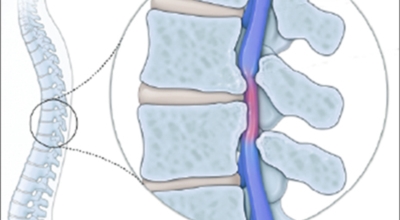

척추관 협착증이란 신경이 지나가는 통로인 척추관이 좁아진 상태를 말하며 척추관 협착증이란 용어는 주로 요추부(허리)에서 사용합니다. 척추관 협착증 환자는 정상에 비해서 척추관이 좁아져 신경이 압박받게 돼요.

정상인 사람은 척추가 완만히 휘어져 있는데 척추관 협착증인 사람은 더 일자로 펴져 있고 정상인 사람의 척추관은 공간이 적당한데 비해 척추관척 협착증인 사람은 척추관이 일그러져 있어요. 척추관 협착증 환자는 자기 공명 영상(MRI)에서 보면 척추관 내 신경을 싸고 있는 경막 안에 정상에서 보이던 뇌척수액이 보이지 않는다는 특징이 있어요.